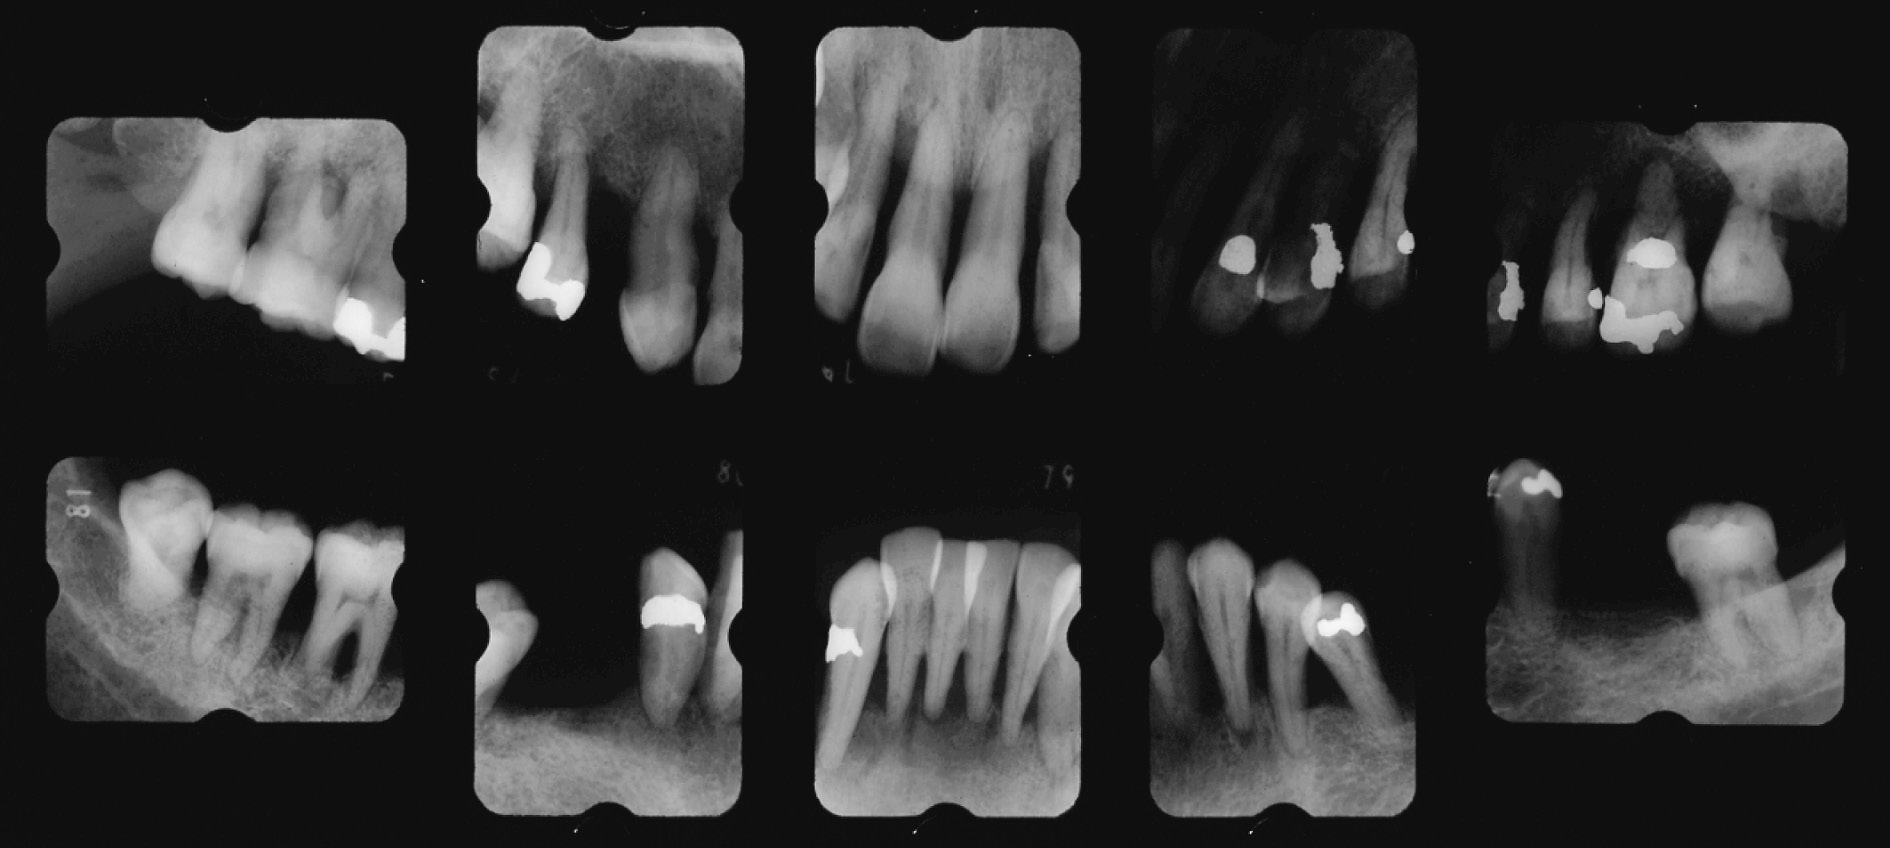

c) 治療経過とSPT重度の広汎型慢性歯周炎患者の初診時の病態写真(図7)とエックス線写真(図8)で,病態写真は一部紛失している。近隣歯科医の下でプラークコントロールや縁上スケーリング処置は受けたものの,外科処置やリコールの設定がなされなかったものである。高度な歯周組織破壊と著しい歯肉退縮が特徴である。ただ,動揺の揺れ幅や安定性に関しては頬舌方向の揺れより近遠心方向の揺れが明らかに少ない。14,35,44,45に歯の欠損があるものの,歯列の連続性が保たれていて,咬合圧等の外力に連座して抵抗できていたものと考える。そこで,二次性咬合性外傷への対策およびブラッシング時の機能的動揺への不安軽減を考慮して,計画の最重要点として,①隣接面を共有する全歯への暫間固定(前歯B-スプリント,臼歯A-スプリント),②欠損部への暫間義歯の装着の2つを掲げて処置を継続した。プラークコントロールは常時良好で,PCR値は10%前後に落ち着いていた。

初診時のエックス線写真(51歳,女性)。